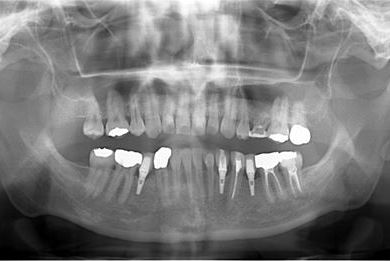

骨再生インプラント治療

| 治療方針 | ソケットリフトにて上顎洞を拳上し、インプラント治療を可能にする。 | ||||||||||||||||||||||||||||||||

| 治療内容 | インプラント1本(ソケットリフト)、メタルボンドセラミッククラウン1本 | ||||||||||||||||||||||||||||||||

副作用・リスク

インプラント治療の副作用・リスクについて

インプラント埋め込み施術は外科治療のため、腫れる可能性があります。細菌感染すると施術のやり直しになりますが、当院では洗浄・滅菌を徹底して感染リスクを抑えます。また、インプラント周囲炎にならないために、通常の歯と同じように丁寧なブラッシングや定期メンテナンスが重要となります。